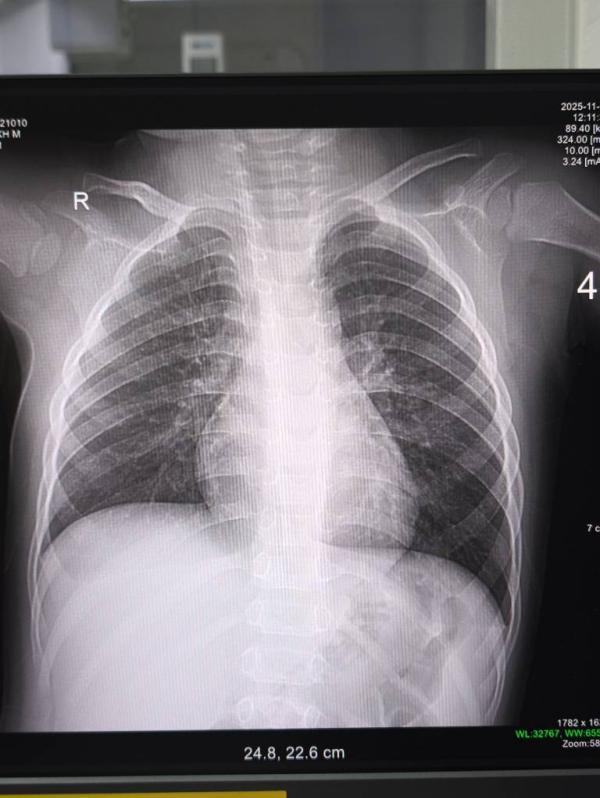

Рентген у ребенка: безопасно ли это для здоровья малыша?

Д1е дик хил. Кто разбирается,норм ли рентген у ребенка ? А то ответа ждать надо